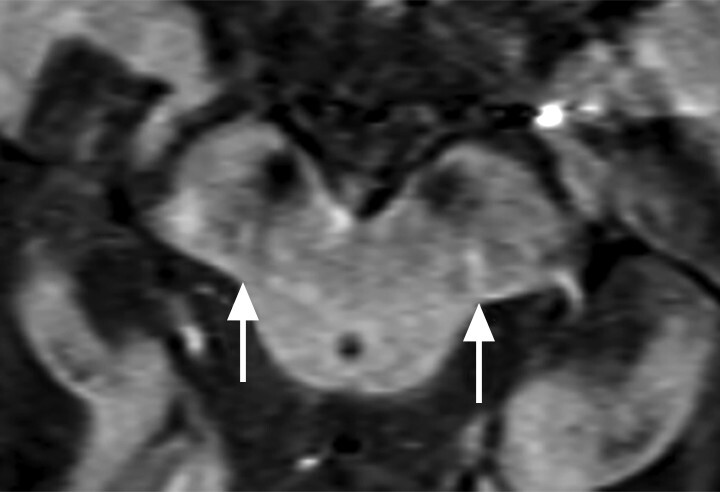

- Der Nachweis der Degeneration des dopaminproduzierenden Nigrosoms 1 innerhalb der Substantia nigra und des damit verbundenen Verlusts des Schwalbenschwanzzeichens (Swallow Tail Sign; Abb. 69.2) zeigt keinen eindeutigen Mehrwert in Bezug auf Diagnose und Differenzialdiagnose von Parkinson-Syndromen. Die Beurteilung des Schwalbenschwanzzeichens ist nämlich deutlich scanner- und befunderabhängig und wird in bis zu 50% der Fälle auch bei Patientinnen und Patienten mit frontotemporaler Demenz und Alzheimer-Demenz als anomal eingestuft [12].

Abb. 69.2 Parkinson-Syndrome.

a Schwalbenschwanzzeichen beidseits als Ausdruck eines unauffälligen dopaminproduzierenden Nigrosoms 1 (Pfeile).

b Beim idiopathischen Parkinson-Syndrom, aber auch bei anderen neurodegenerativen Erkrankungen, ist das Schwalbenschwanzzeichen (Swallow Tail Sign) in der SWI-MRT (Schichtdicke 2 mm) einseitig oder beidseitig nicht abgrenzbar (Pfeile).